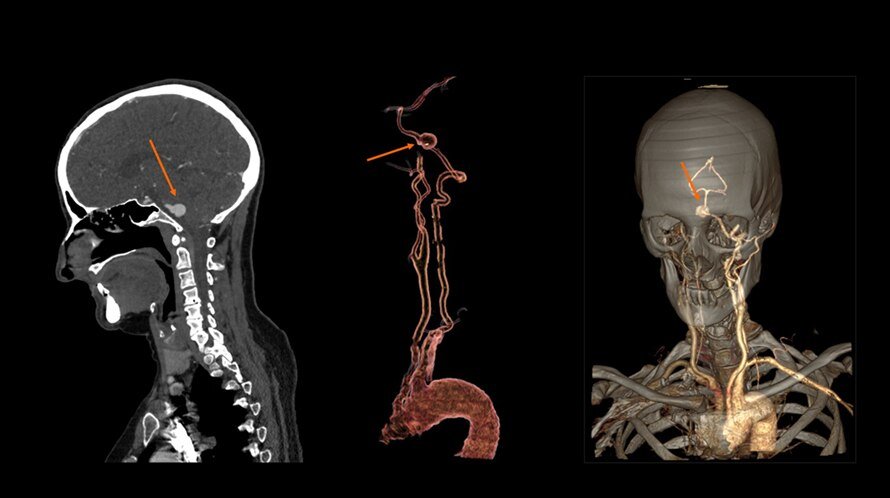

Optima ct520

Optima ct520 115 фото